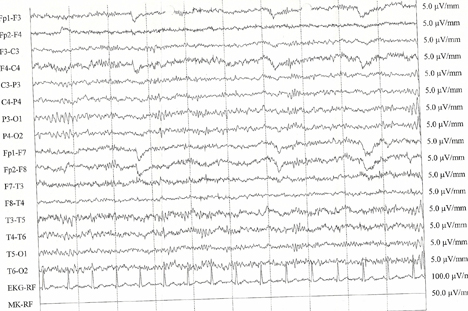

Se réveillera-t-il un jour du coma? Répondre à cette question représente un défi de taille pour les médecins, tant ce dysfonctionnement cérébral est complexe. Grâce à de nombreuses recherches et des appareils toujours plus précis, le coma se dévoile progressivement. «Depuis 2010, nous effectuons une batterie de tests à l’aide d’un électroencéphalogramme sophistiqué, qui nous permet d’établir une carte détaillée du cerveau, explique Mauro Oddo, responsable de l’Unité de neuroréanimation du CHUV. Nous soumettons les patients à une série de stimulations sensorielles et observons leurs réactions. A partir de là, il est possible de prédire si un patient ne va pas se réveiller avec une probabilité de plus de 80%, notamment dans un coma post-arrêt cardiaque.»

Le test consiste à soumettre les patients à divers stimuli auditifs, puis à observer la réaction de leur cerveau grâce à un électroencéphalogramme. «Dans la phase des soins intensifs, nous plaçons les patients en état d’hypothermie pendant douze heures et abaissons la température de leur corps à 33 °C, détaille Mauro Oddo. Ce traitement permet de préserver les fonctions cérébrales. C’est à ce moment que nous commençons à observer le cerveau de la personne, en observant sa réaction à une série de sons monotones, qui varient dans leur intensité et leur durée. «24 heures plus tard, alors que le patient a été réchauffé et a retrouvé une température normale, l’équipe médicale répète le test. Lorsqu’elle a observé une amélioration entre la première et la seconde session, les comateux se sont pour l’instant toujours réveillés.